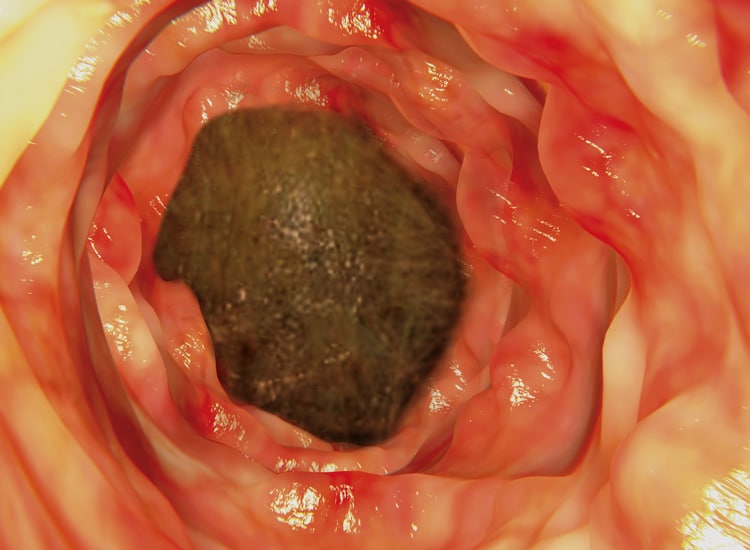

Cette dernière s’avère être le seul moyen pour résoudre l’affection sauf si le corps étranger n’est pas vulnérant (qui blesse) et se situe dans la portion haute du tube digestif (estomac, début de l’intestin grêle) et peut être extrait sous endoscopie : une exploration à l’aide d’un endoscope permettant de visualiser l’intérieur du tube digestif et qui nécessite une anesthésie générale.

3 • Incision de la paroi intestinale avec un bistouri.

4 • Retrait du corps étranger de l’intestin à l’aide d’une pince.

5 • Corps étranger extrait.